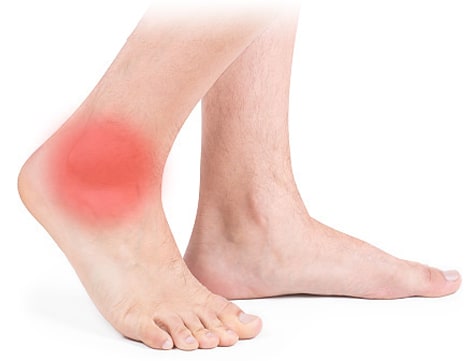

7. 고관절 통증 증상 - 엉덩이·허벅지·종아리 통증이 동반될 때

이 경우에는 허리 디스크나 척추 협착 같은 척추 질환이 함께 있어 신경 증상이 고관절 통증으로 이어지는 경우가 많습니다. 오랫동안 서 있거나 앉아 있는 자세, 잘못된 체형 유지, 또는 통풍·류머티스 같은 전신 질환 등이 원인이 될 수 있습니다. 신경 압박으로 허벅지와 종아리에 방사통이 나타나며 골반 부위에도 통증을 유발할 수 있습니다.